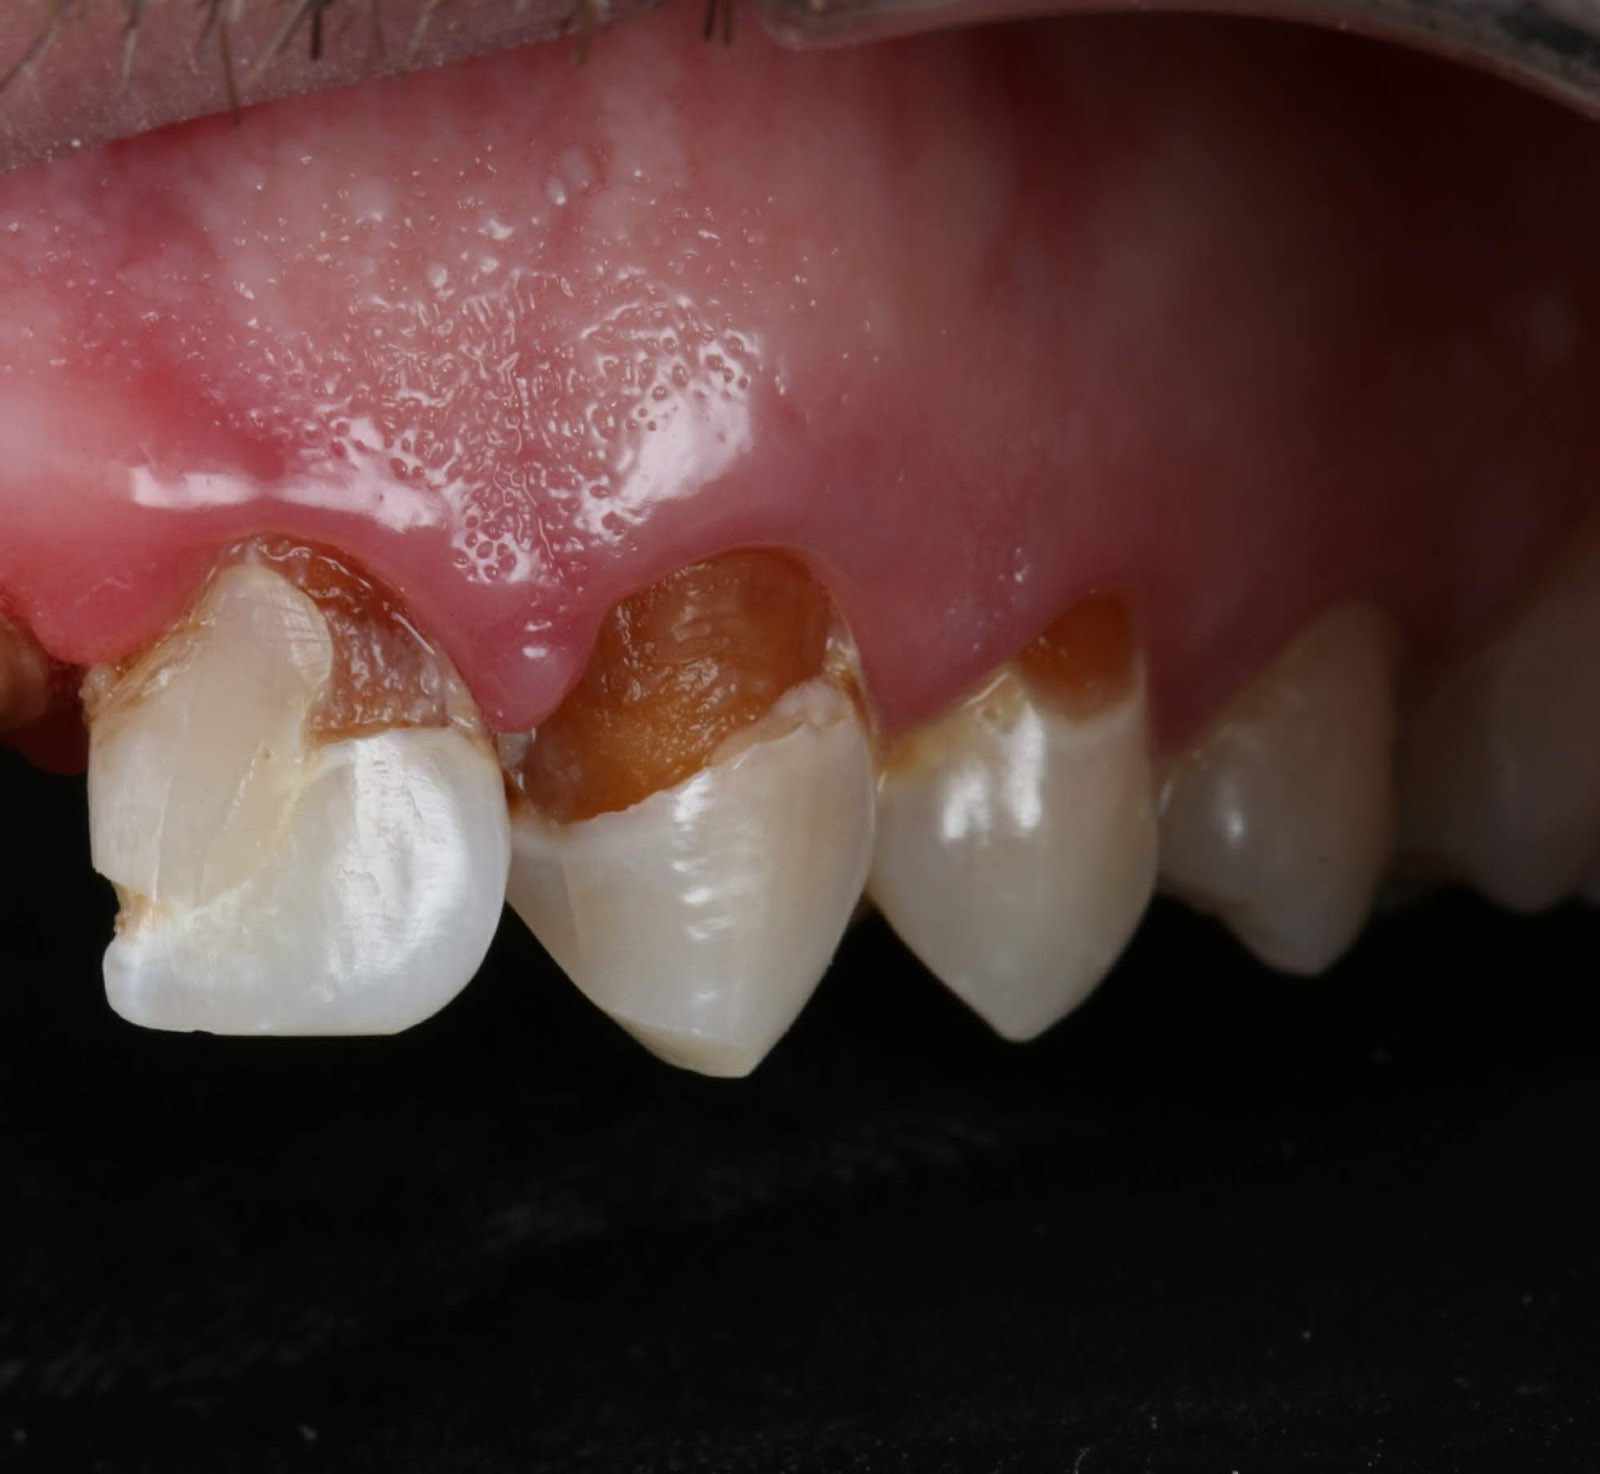

Generalized Periodontal Disease

Generalized periodontitis is a severe form of gum disease that affects multiple teeth and is treated with deep scaling and root planing (see Figure 9). It presents as rapid progression of periodontal tissue destruction, which leads to tooth loss if not treated.

Figure 9. Generalized Periodontal Disease |

![]() |

Clinical and radiographic example of periodontal disease |

Source: DRosenbach. https://creativecommons.org/licenses/by-sa/4.0/deed.en |

Generalized periodontal disease is caused by a bacterial infection (primarily anaerobic bacteria), hormonal changes (e.g., pregnancy, menopause, genetics), smoking, and diabetes. The patient presents with red, swollen, bleeding, and tender gums. On examination, the patient will have periodontal pockets in excess of 5 mm. The gingiva may bleed, especially when brushing or flossing. The patient may complain of bad breath and loose teeth. A referral to a dentist or dental hygienist is indicated for X-rays and comprehensive dental cleaning.

Antibiotic therapy, as well as scaling and root planing by a hygienist or periodontist, or periodontal surgery by the periodontist, generally is indicated. Lifestyle changes (e.g., smoking cessation, improved oral hygiene, healthier diet, and regular dental check-ups) are necessary to prevent periodontal disease from recurring. If not treated, periodontal disease can lead to tooth and bone loss and an increased risk of heart disease and stroke.2,4,5